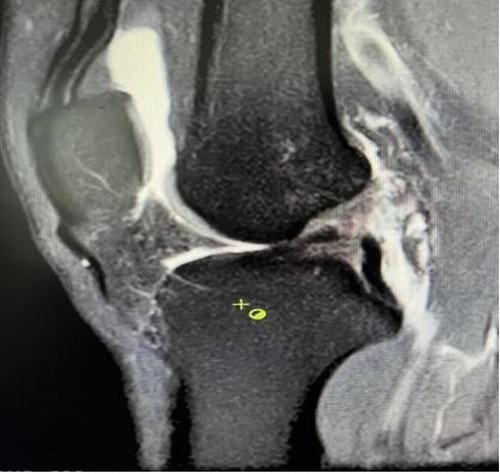

膝關節(jié)韌帶損傷磁共振

我院骨科三病區(qū)近期收治了4名膝關節(jié)交叉韌帶損傷患者。25歲的齊先生,因打籃球時不慎扭傷左膝,致右膝腫痛,遂來我院治療;30歲趙先生酷愛足球,扭傷右膝關節(jié)來我院就診;50歲的張先生、42歲劉先生因騎車滑倒摔傷、膝關節(jié)腫痛不適、活動受限,收治入院。骨科三病區(qū)李鵬主任團隊詳細查體以及完善影像學檢查后進行診斷:幾位患者共同診斷均有“前交叉韌帶損傷”,不同程度合并有“半月板損傷”、“股骨軟骨損傷”、“內(nèi)側副韌帶斷裂”。